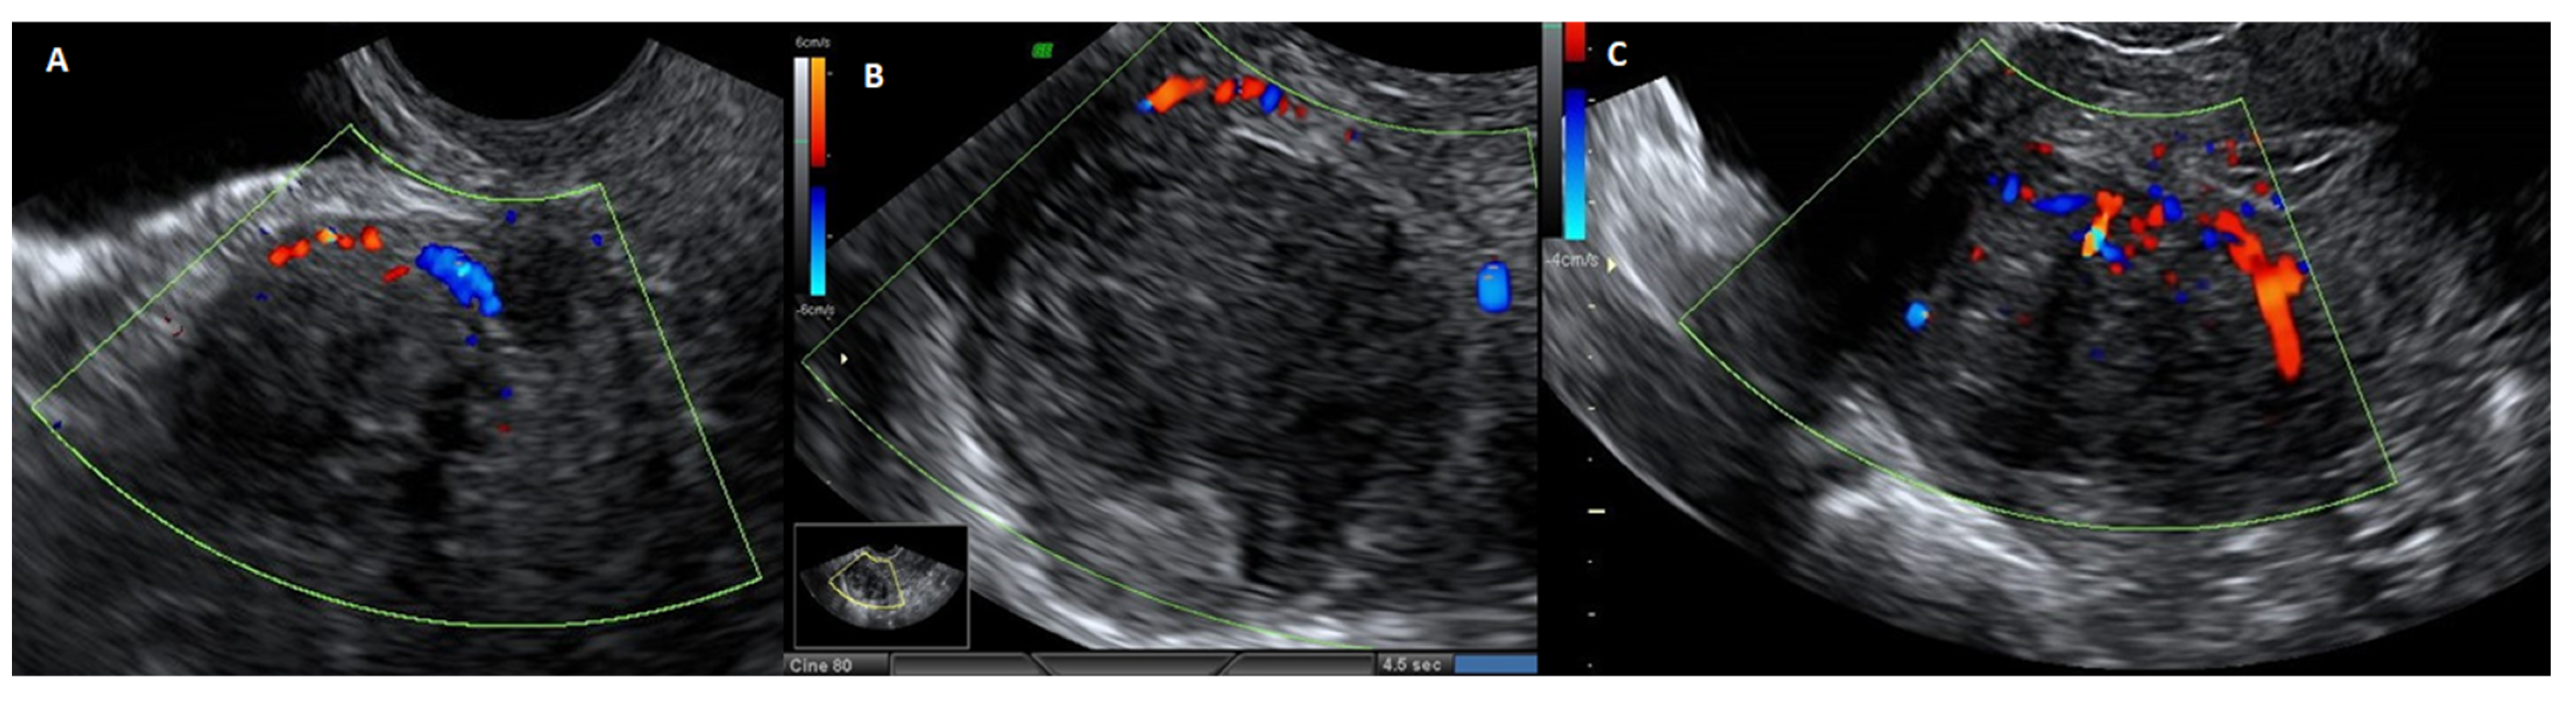

The veins surrounding the myoma circulate beneath the pseudocapsule, which is arranged in a plexus, and the biochemical growth factors evaluation in pseudocapsule vessels revealed intense angiogenesis [38]. The pseudocapsule vessels, which originate from the surrounding myometrium, throw themselves in a group to the center of the vascular network (Figure 5).

Figure 5.

Ultrasound image with echodoppler of fibroma with overlying pseudocapsule: (A) on the left, vascular ring of fire of the pseudocapsule, which is included in the vascular ring; (B) in the center, fibroma without internal vascularization; (C) on the right, the vascular ring of fire of the pseudocapsule, with vessels detaching from the pseudocapsule and penetrating from the periphery of myoma towards the center of the fibroma.

The development of a “protective” vascular capsule that supplies blood to the expanding tumor is most likely the result of the angiogenesis of the myoma pseudocapsule [39]. The myoma pseudocapsule, a type of neurovascular bundle that is abundant in neuropeptides and neurotransmitters, plays a critical role in innervation repair and wound healing, as well as in subsequent sexual and reproductive functions [40]. Neuropeptides and neurotransmitters, including substance P (SP), calcitonin gene-related peptide (CGRP), neuropeptide Y (NPY), oxytocin (OXT), vasopressin (VP), PGP 9.5, and growth hormone-releasing hormone (GHRH), are implicated in muscle repair phenomena and wound healing [41]. Since the majority of these neuropeptides have been highlighted in the myoma pseudocapsule, preserving them during myomectomy encourages appropriate myometrial post-surgical repair [42].

Transabdominal and transvaginal sonography reveals the pseudocapsule as an echogenic line encircling the myoma, with a wall that is at least one centimeter distinct and augmented by distal echoes. In ultrasound Doppler imaging, the myoma pseudocapsule manifests as a “ring of fire”, whereas histological images reveal a clear demarcation separating it from the myometrium. Although the myoma pseudocapsule’s vasculature may have structural flaws that make it brittle, the pseudocapsule is composed of the same cell types and exhibits the same biological structure as the nearby myometrium [37].